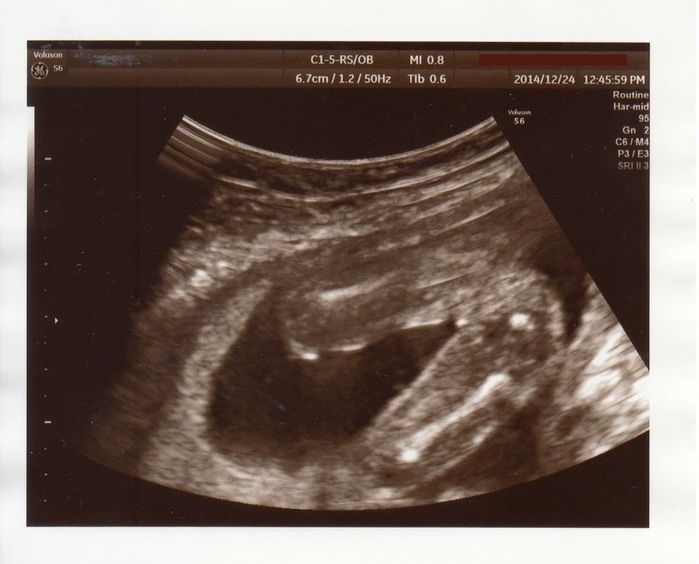

性別判明、女の子でした - 妊娠19週目のエコー写真

このエコー、わかりにくいかも知れませんが、太ももとお股だけの画像です。右側がお股、そこから左に向かって2本の足が伸びています。太ももから先は、写っていない状態。性別が分かる頃なので、そのあたりを中心にエコーを写してくれました。お股に何もないので、女の子ですねと言われました。この頃、戌の日のお参りに行き、安産で無事に生まれますようにとお願いしました。